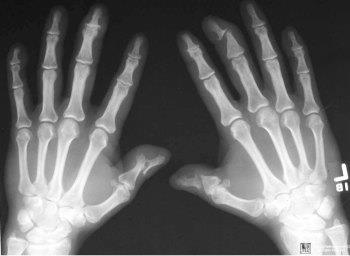

На поздних стадиях отмечается разрушение суставов вплоть до значительных деформаций конечностей. Такой вид псориаза называется деструктивным артритом. На фото псориаз суставов выглядит как саблевидные ноги, ходьба напоминает позу наездника.

Основным инструментальным методом исследования является рентгенография. Данный анализ позволяет установить степень поражения суставов, тяжесть процесса и поможет подобрать наиболее подходящее лечение.

Диагностика псориатического артрита во многом основана на наличии ряда характерных рентгенологических признаков заболевания: